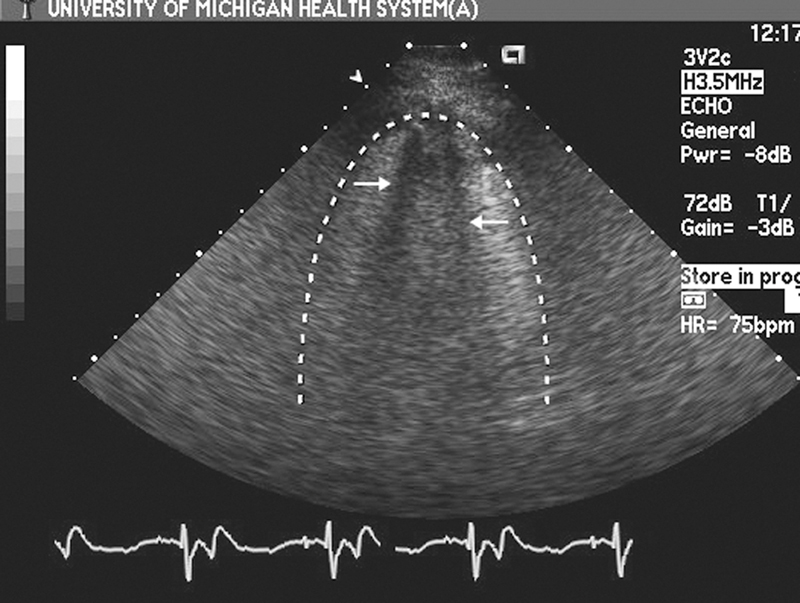

فحوصات تشخيصية لبعض امراض القلب والشرايين التاجية